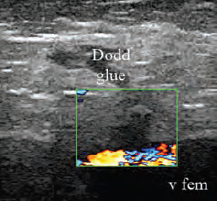

3. ábra.

Dodd perforans véna ragasztós elzárás utáni ultrahang képe. A v. femoralisban jó áramlás.